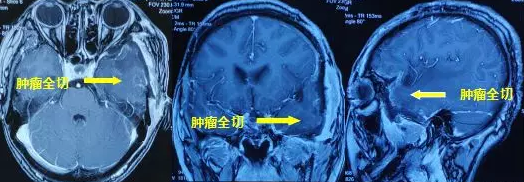

一个月前,47岁的张大姐不幸遇上车祸,在当地医院进行右胫骨上段骨折切开复位内固定术。住院期间,头颅MRI检查提示左颞叶占位。骨折好转出院后,为进一步检查脑袋里面的问题,张阿姨来到重庆主城,在外院行头颅MRI 检查提示"左侧颞部占位,考虑偏恶性肿瘤性病变,脑膜瘤?血管外皮细胞瘤?"

肿瘤周围水肿明显中线移位

水肿消退,中线基本回位

术后恢复较好,复查核磁提示肿瘤切除满意,水肿明显消除,中线基本回位。病检结果提示血管瘤型脑膜瘤,WHO Ⅰ级。